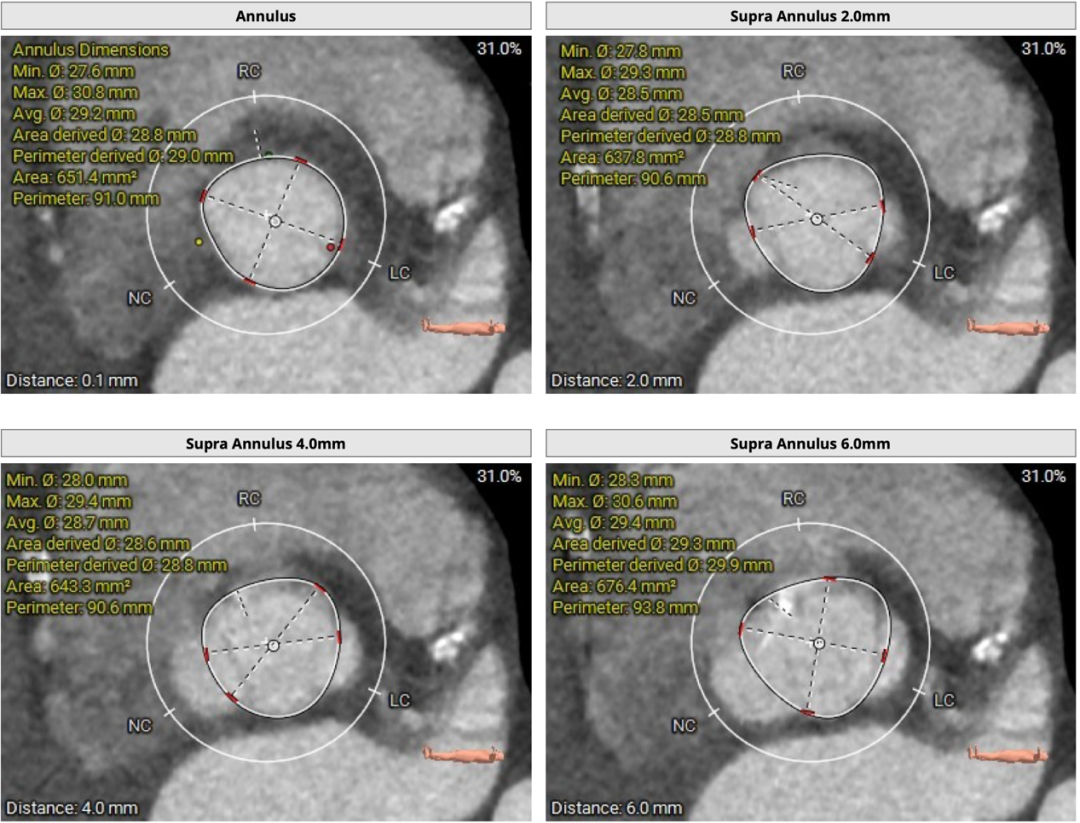

患者主动脉瓣三叶式,瓣叶基本等大,瓣叶稍厚,右无冠瓣瓣叶游离缘轻度钙化,瓣叶交界钙化有融合;主动脉瓣环周长折算直径约29.0mm:

双侧冠脉开口高度可,LCA 11.5mm, RCA 18.7mm;右冠、左冠及分支轻度钙化:

术中建议造影角度LAO 4°,CAU 6°(其它考角度如下图):

横位心,心室角度68°: